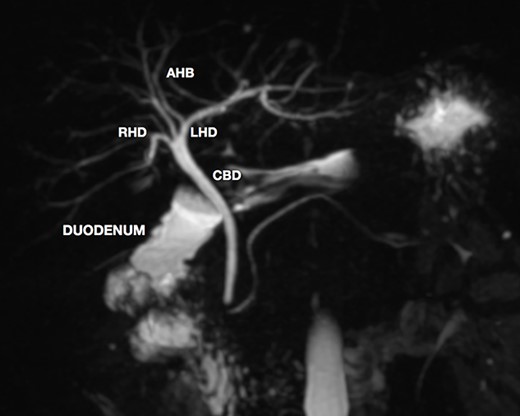

A magnetic resonance cholangiopancreatography (MRCP) confirmed the absence of gallbladder and of the cystic duct and artery (Figs 4–6). No other abdominal anomaly was identified.

MRCP coronal image showing the common bile duct, portal vein, duodenum, liver and other close structures; there is no sign of gallbladder.